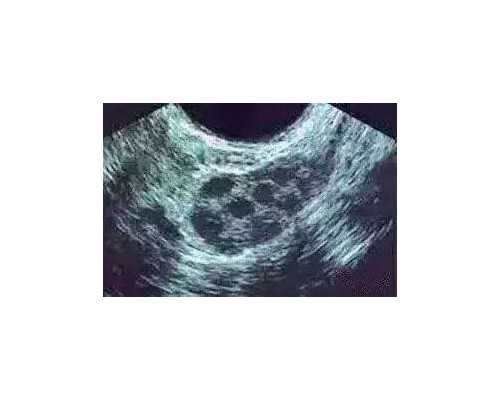

先进设备保障手术顺利进行 广东的不孕不育医院拥有先进的设备和技术,如超声引导取卵技术、胚胎移植技术等。这些设备可以确保手术过程的准确性和安全性,提高试管的成功率。